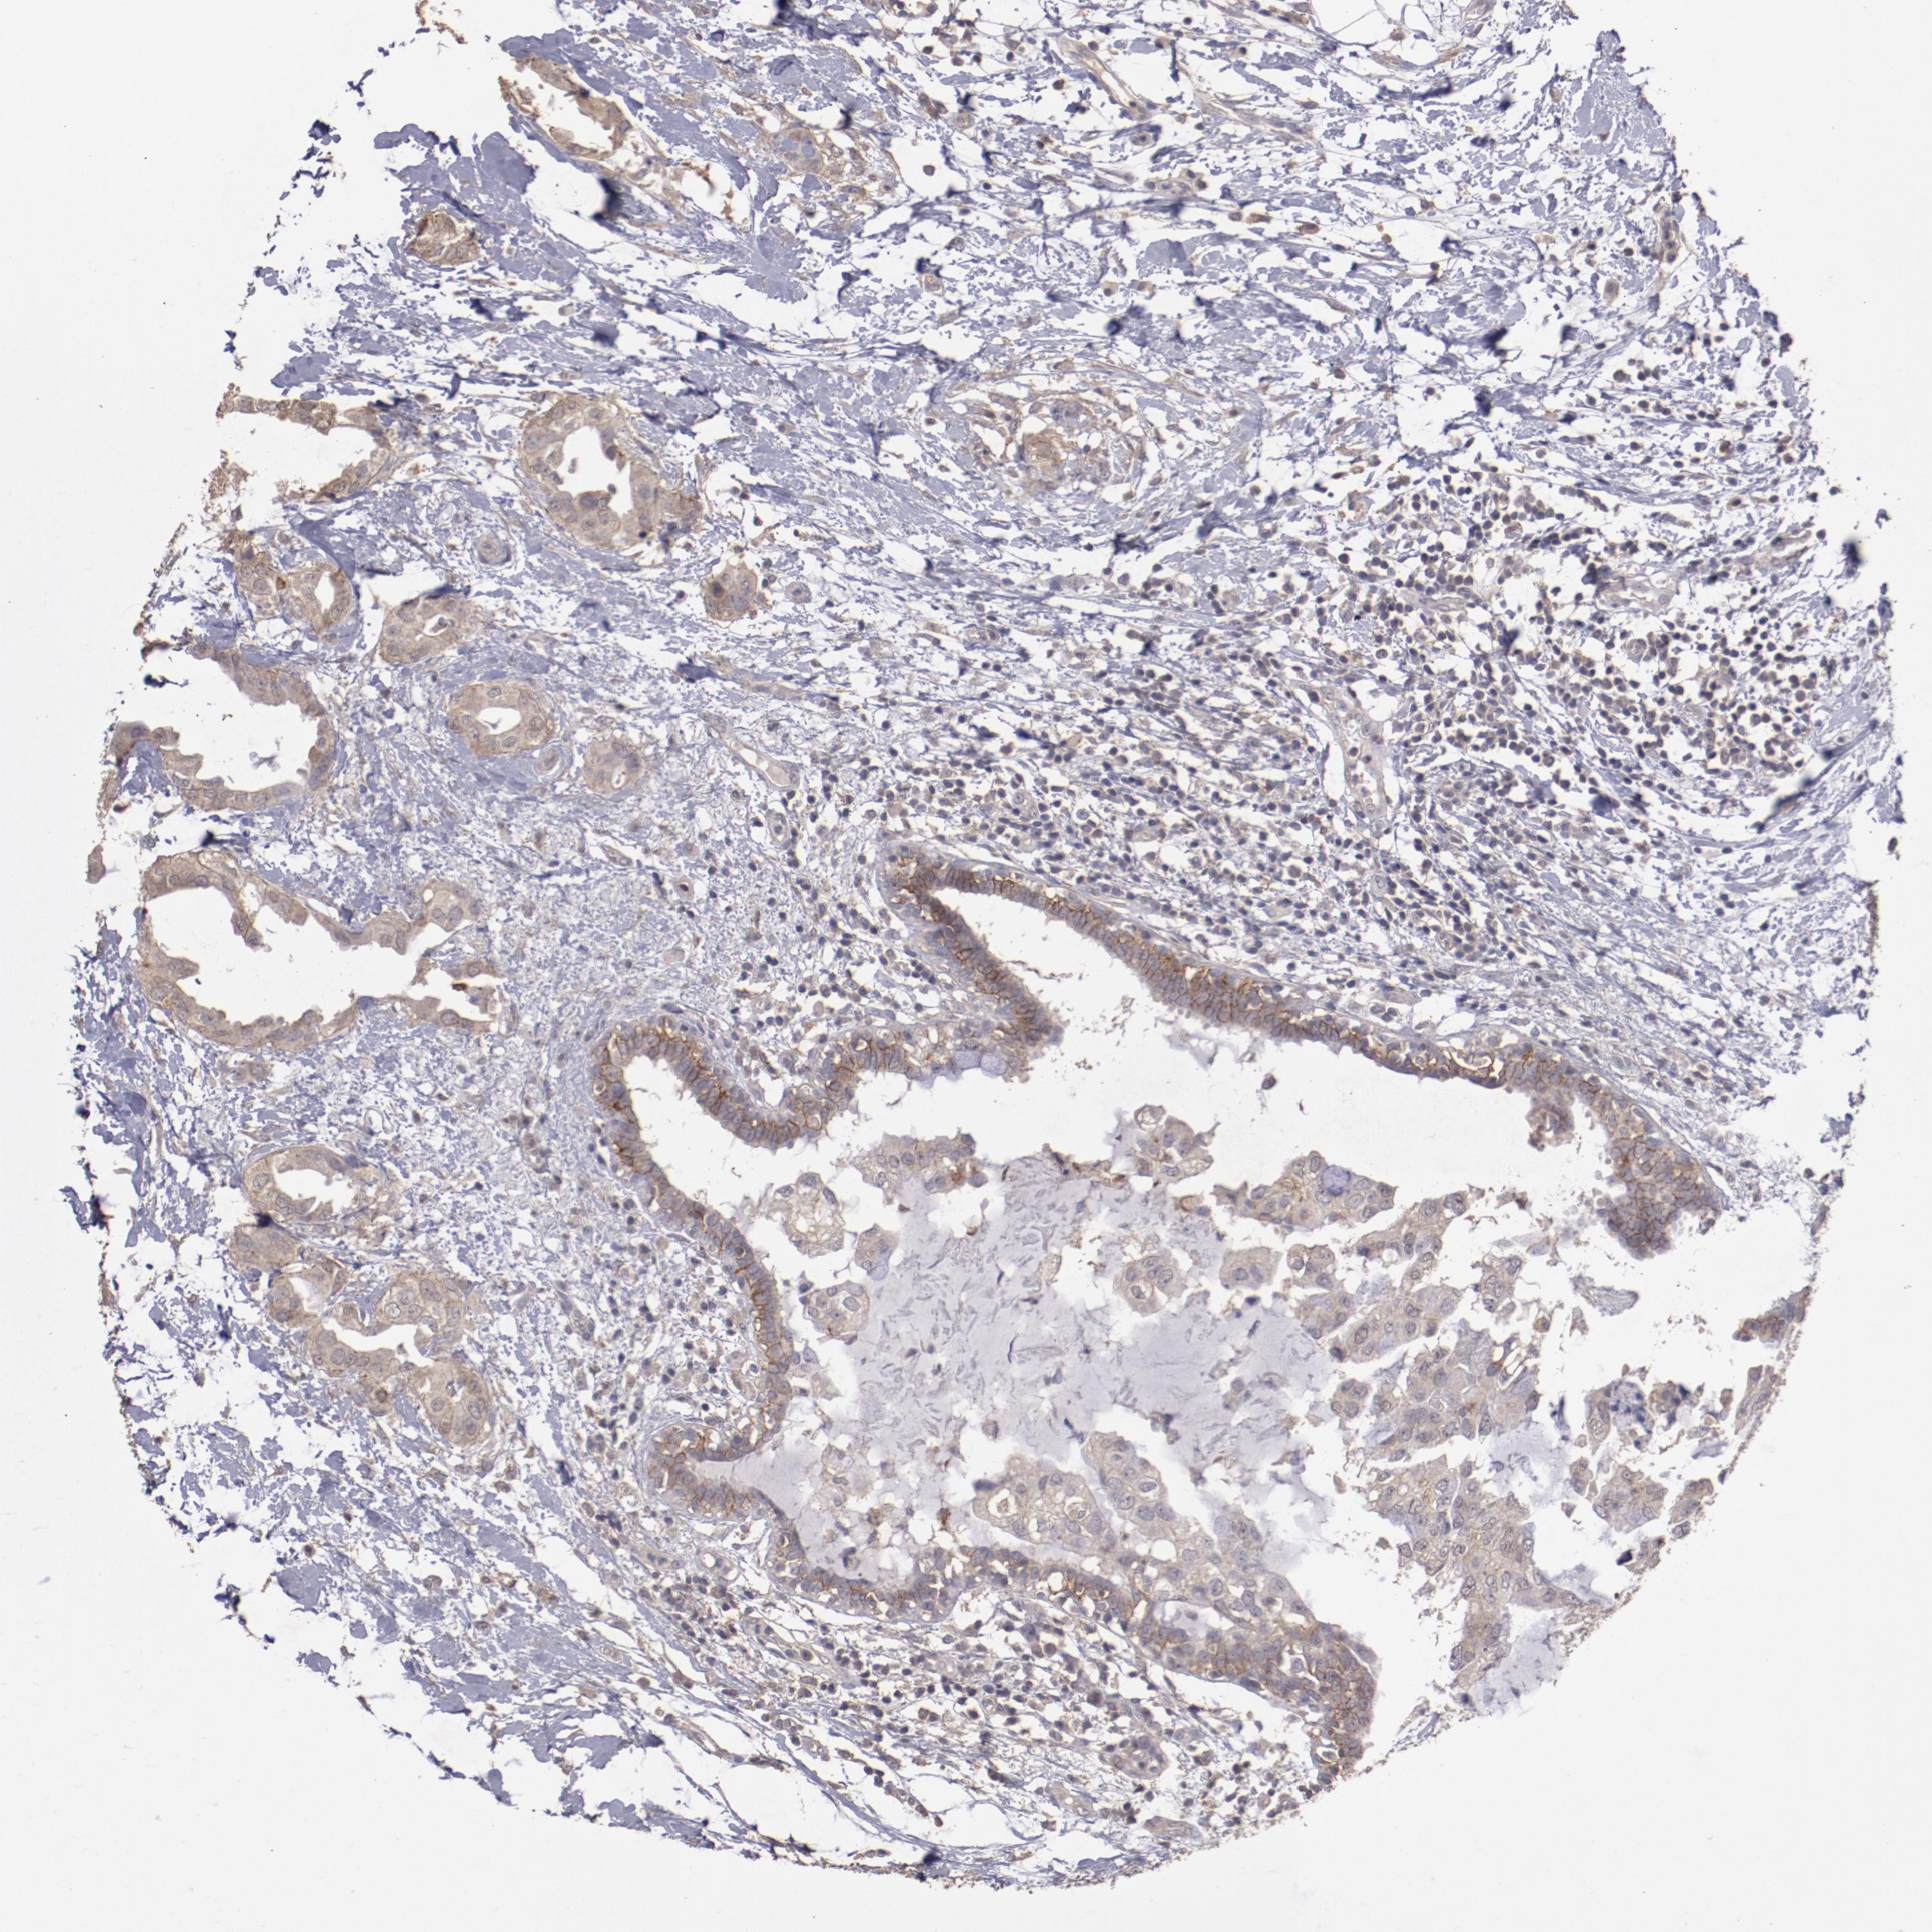

BRCA TCGA BRCA VALIDATION PROTEIN EXPRESSION

ANTIBODIES

AND

VALIDATION